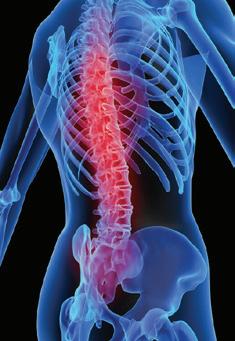

It is 40 years since the first critical illness cover plans came to Britain and much has changed since then. 40 years ago, 1 in 5 were likely to be diagnosed with cancer; shockingly, in 2024 that statistic is 1 in 2.

What has changed? More data is available today and more life-saving treatments, therefore more claims is a factor. Poor diet, lack of exercise are others. Once, a major illness would have a greater probability of turning into a death claim, not a critical illness claim. Modern medicine means more illness is diagnosed but equally more are treated, meaning fewer death claims.

Historically, people bought critical illness as a bolt-on to their life cover, usually because of insuring the mortgage in event of an early unexpected demise. In event of death during the remainder of the mortgage term, the life cover would hopefully be sufficient to pay off the remaining mortgage debt, so the house could be passed on debtfree to surviving family members.

Upon diagnosis of a major specified illness, the critical illness cover would pay a tax-free lump sum to the policy holder whether death was a consequence or not. As advisers, we would normally advise the critical illness aspect to protect and pay off any mortgage or other debt.

However, in the event of a claim, it is not compulsory how critical illness claim monies are spent. According to CIExpert Critical Thinking Report 2024, less than 20% of claimants used claim funds to pay off mortgage debt. Instead, it is more popular to use the funds to pay for or towards private medical treatment, replace lost earnings, help improve or aid their health or save it for the future. So, whilst not the intended design for the plan (often the cover reduces aligned to the reduction in mortgage owed), claimants use it for other purposes. It is their money after all. Why not consider Private Medical

Insurance which is designed to do that job more effectively with often more support and benefit than simply receiving a tax-free sum? Ideally PMI is a complementary insurance to run alongside your mortgage cover to help fund treatment and support such as access to GPs within 24 hours as well as paying for medical assistance and operations/treatments.

We are all well aware of the intense pressure on the NHS to deliver services and we hear regularly of waiting lists of 2 years plus for hip and knee replacements. To fund privately would cost around £10-£15k per limb. There is likely to be no quick-fix to hospital waiting lists, despite various political parties claiming to have the answer. In the meantime, those on the lists are suffering or treatment can be fatally delayed. As an adviser I have had a lot of PMI enquires in 2024 whereby the client has decided the cost of the delay was more than they were willing to bear and so PMI is very popular.

Without suitable insurance cover, what costs of living would you be willing or unwilling to manage without? The same Report asked what people would give up or cut back on and said 68% were unwilling to get rid of broadband, 58% reduce heating/energy.

Modern insurance plans have many added value services such as access to GPs, counselling, prescription services and health MOTs as offerings. What is the value of these to you? How do you define ‘value’? More food for